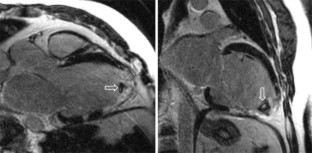

Die Indikation zur kardialen Magnetresonanztomographie (CMR) besteht in erster Linie, wenn eine pharmakologische Belastungsuntersuchung indiziert ist. Mit Dobutamin durchgeführt ist die CMR dann eine Alternative zur Echokardiographie, während die Adenosin-Perfusions-CMR die strahlenfreie Alternative zur Myokardszintigraphie darstellt. Die CMR-Spätaufnahme nach Kontrastmittelgabe stellt den Goldstandard für die Darstellung myokardialer Narben und die Vorhersage einer Erholung der myokardialen Funktion nach Revaskularisierung (Vitalitätsuntersuchung) dar.

The main indication for cardiac magnetic resonance imaging (CMR) is for pharmacologic stress testing. If such a test is indicated, dobutamine stress CMR is an alternative to stress echocardiography and adenosine perfusion CMR is the alternative to nuclear myocardial perfusion imaging but without radiation. Late gadolinium enhancement CMR is the current gold standard for the assessment of myocardial scars and hence is well suited to predict recovery of function in dysfunctional myocardial regions following revascularisation (viability testing).